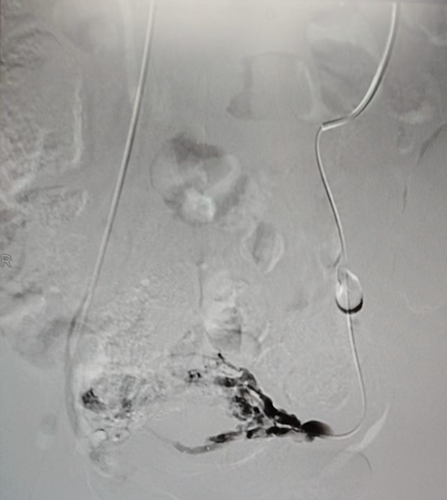

手术台上,张涛教授化身“血管工程师”,在局麻下为小雪实施了“腔静脉、盆腔静脉造影 + 盆腔静脉栓塞术”。

手术过程中,静脉造影就像给血管来了一场 “高清直播”,清晰地展示出左侧卵巢静脉明显迂曲增粗,造影剂滞留延迟,盆腔静脉丛血流瘀滞,左侧卵巢静脉丛多处病灶更是呈现出团状迂曲增粗、侧枝丰富的“乱象”。

发现 “罪犯血管” 后,张涛教授凭借精准定位,采用泡沫硬化剂联合弹簧圈栓塞术,直接阻断其血供,彻底切断“罪犯血管”的“通路”。